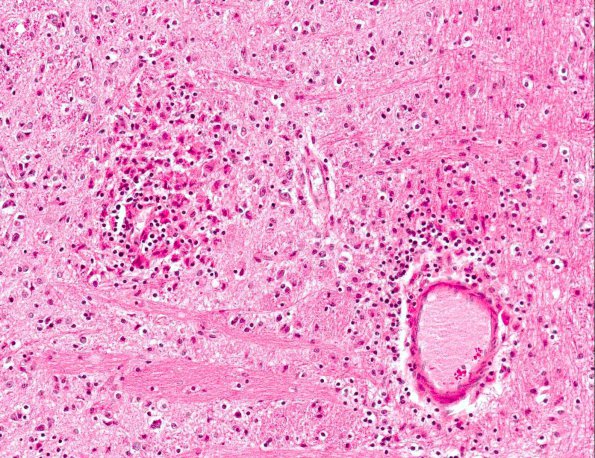

Washington University Experience | MISCELLANEOUS | Familial erythrophagic lymphohistiocytosis | 2A4 Familial erythrophagic lymphohistiocytosis (AANP 1980, Case 2) H&E X20 2

Higher magnification of the pontine pathology shows perivascular collections of an inflammatory infiltrate consisting of histiocytes, lymphocytes and mononuclear cells. The integrity of the vessel wall is relatively well preserved (H&E)